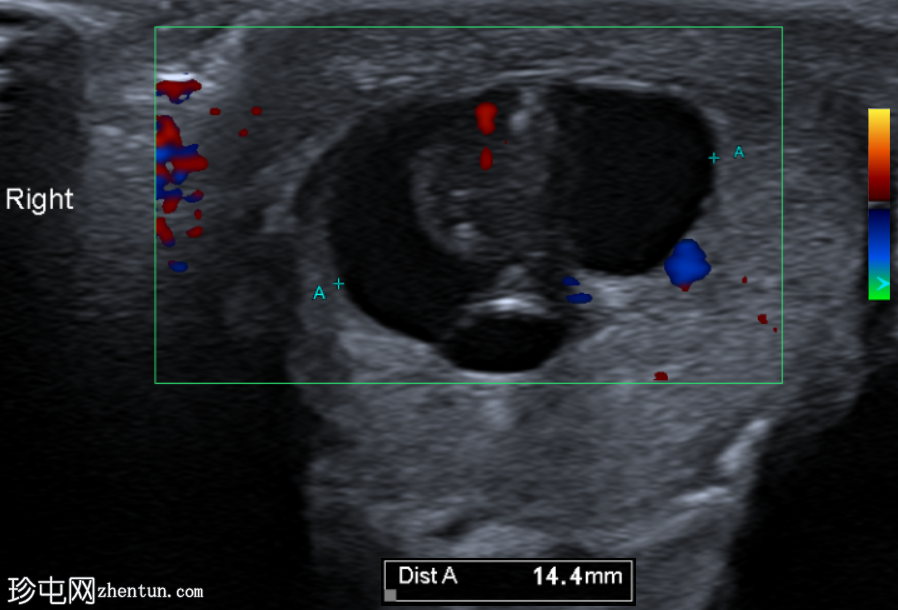

纵切面

右侧睾丸内可见一异质性肿块,大小约10 x 14 x 15 mm,包含实性和囊性成分。肿块内可见多发小钙化灶。彩色多普勒超声检查显示肿块内血流信号较少。